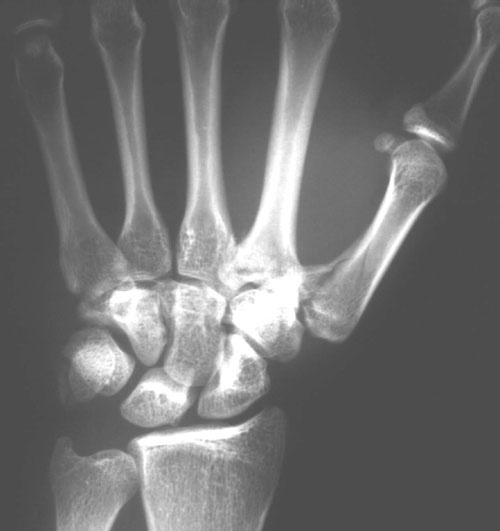

本耐氏bennett骨折即第一掌骨基底部骨折伴脱位

bennett骨折影像评估